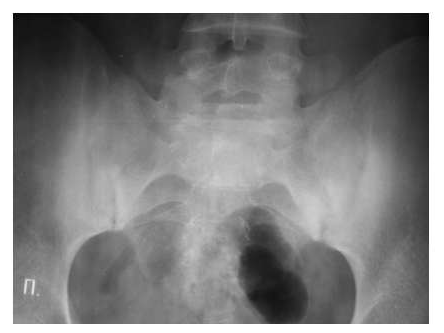

Для серонегативных спондилоартритов более типичным является наличие эрозий суставных поверхностей в дистальных отделах стоп.

Рис. 7. Двусторонний сакроилиит у больного серонегативным спондилоартритом.

Околосуставной остеопороз в отличие от РА выявляется только в острую стадию артрита. Одна из основных локализаций, где развиваются костные пролиферации - это краевые отделы крестца и подвздошных костей (рис. 7).